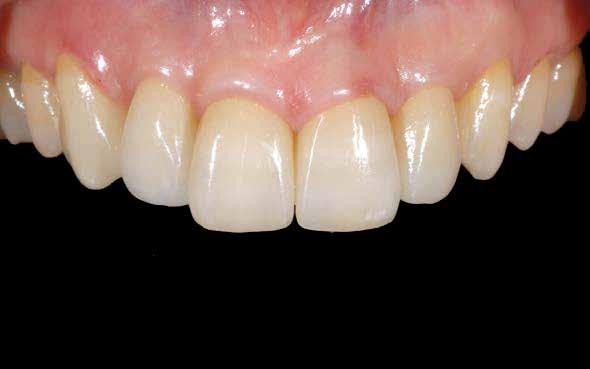

Fiatal frontfogak – régebbi gyakorlómunkák, préskerámiából készítve, csak festve

Zárókép idősebb frontról